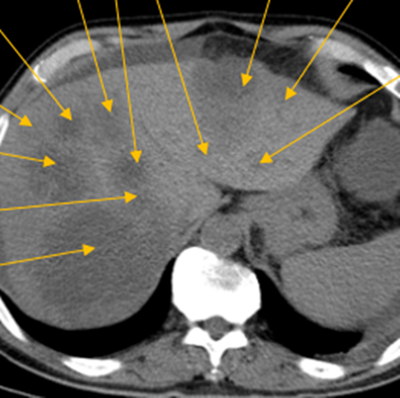

治療前:箭頭處均為轉(zhuǎn)移性腫瘤

隨后,根據(jù)基因檢測(cè)結(jié)果制定了化療+靶向治療方案。經(jīng)過(guò)精準(zhǔn)治療,劉大爺?shù)牟≡畲笮⊙杆倏s小,病灶數(shù)量不斷減少,影像學(xué)評(píng)估已經(jīng)看不見(jiàn)之前那些小的病灶了。